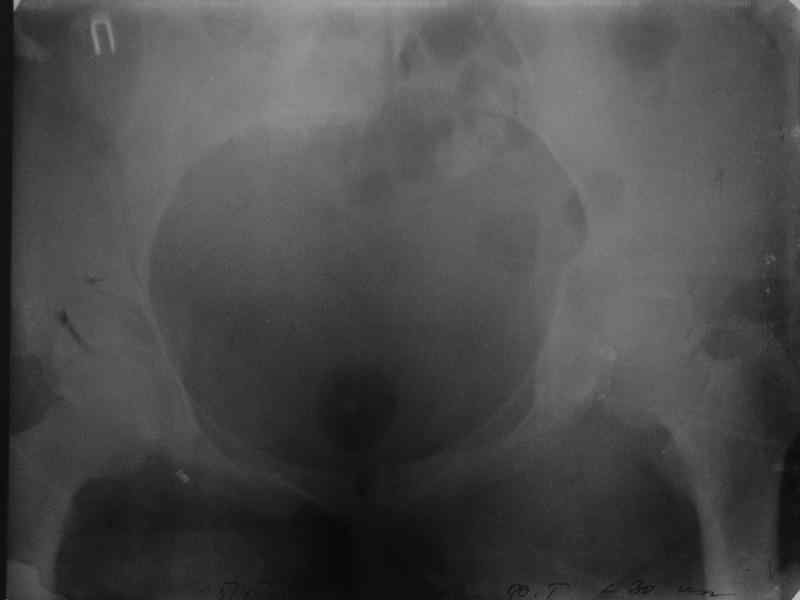

Здравствуйте, коллеги. Какие будут мнения по поводу лечения представляемой больной?

Молодая девушка 19 лет, травма 1 год назад, тогда же прооперирована.

В настоящее время имеются ноющие боли в области крестца слева, нарушение походки, ощущение неуверенности, слабости в левой нижней конечности, неврологически -непостоянные парестезии в левой нижней конечности. Ходит с дополнительной опорой, страдает от ожирения.

В приложении снимки при поступлении и послеоперационные год назад.